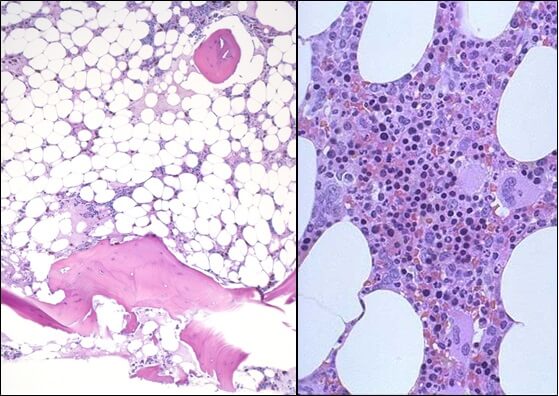

- Исследованиепунктата костного мозга. В миелограмме обнаруживается уменьшение количества миелокариоцитов и мегакариоцитов, снижение клеточности. В трепанобиоптате определяется замещение красного костного мозга жировым (желтым).

При наличии заболевания у пациента выявляют серьёзное снижение гемоглобина, вплоть до критического уровня – 20-30 г/л, наблюдается агранулоцитоз – снижение зернистых лейкоцитов и моноцитов. Количество лимфоцитов может быть в норме или сниженным, тромбоцитов – всегда снижено, иногда их не обнаруживают вовсе. Скорость оседания эритроцитов – повышается до 4-60 мм/ч. Исследование образца костного мозга выявляет повышенное содержание жировой ткани – 90%, включающее в себя элементы стромы и лимфы, а вот гематогенные клетки имеются в очень малом количестве.